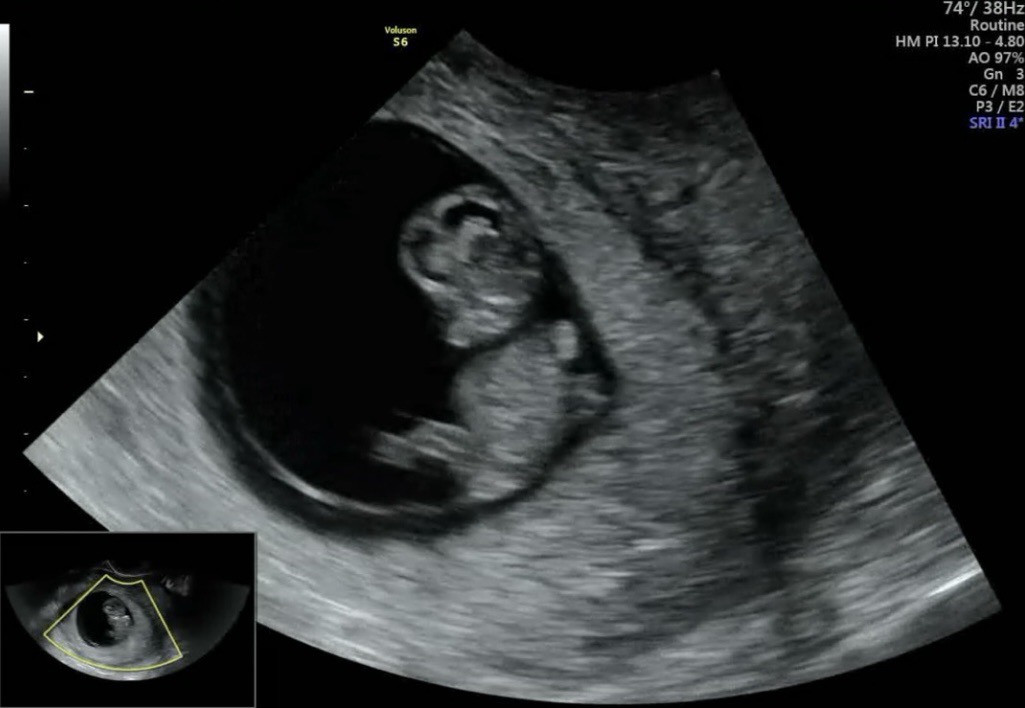

9w4d 발차기하는 젤리곰

어제 오후, 젤리곰 볼 수 있을거라는 의사선생님 말씀에 기대 가득 안고 병원에 왔는데 발차기하는 젤리곰 봤어요 진짜 심장폭격 귀여움이네요 2.7cm인데 손가락 발가락도 생기구 좌뇌 우뇌도 있구 그 조고만 발로 발차기하며 활발하게 놀고 있어요 아 너무너무 귀여워서 심장아파요 😂 요때가 제일 귀여울 때라고 하셔서 스샷 올려요 모두들 선물같은 하루 되세요 💕